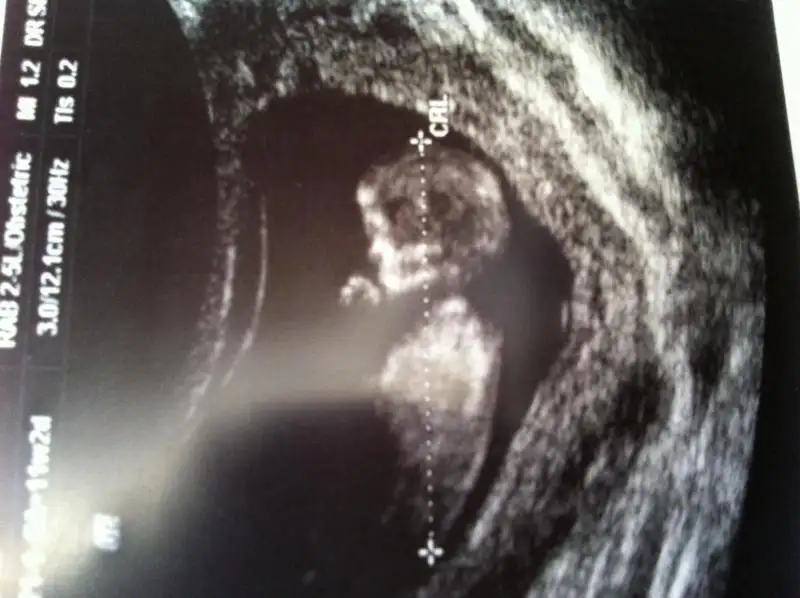

dr soylemeden siz gorun genital nub teorisi ( bebegin cinsiyeti)

Arkadaslar banada tahmınde bulunurmusunuz bebegım kızmı erkekmı cok merak edıyorum orkıde hanım lutfennn tahmınlerınızı beklıyorum